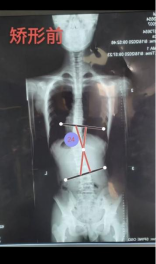

案例3:患者,13岁,青少年特发性脊柱侧弯。考虑其尚处发育期,需兼顾矫正与生活质量的需求,我科室应用3D打印个性化矫形器进行治疗,通过三维扫描获取患者躯干精准数据,经生物力学模拟设计后,3D打印出轻量化、透气且完全贴合的个性化矫形器,不仅实现了显著的即时矫正效果、有效控制了侧弯进展,更凭良好的佩戴舒适度提升了患者依从性。该技术以最小的负担,护航青少年患者的脊柱健康与正常成长,意味着医院逐步形成了脊柱侧弯手术与非手术的完整治疗体系。